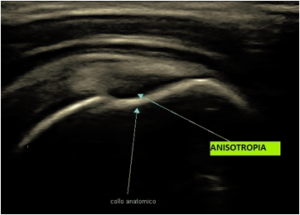

L’ANISOTROPIA e’ un artefatto che puo’ simulare una lesione.

Rappresenta la più comune causa di errore di interpretazione in ecografia muscolo-tendinea.

Essa si verifica quando il fascio di ultrasuoni non è perpendicolare al tendine. In questa circostanza il tendine o una parte di esso, normalmente iperecogeno, diventa anecogeno, simulando una lesione. In questo caso un valutatore con un pò di esperienza sa bene che basta variare l’angolo di incidenza per definire meglio l’area sospetta.

In realta’, durante la valutazione, sono eseguite anche scansioni ortogonali a conferma di lesioni sospette, pertanto in linea generale, NON E’ CONVENIENTE affidarsi ad una singola scansione senza avere la conferma della lesione anche in scansioni tra loro ortogonali e da differenti angolazioni. Solo in questo modo la valutazione puo’ essere certa e puoi essere SICURO di cio’ che vede.